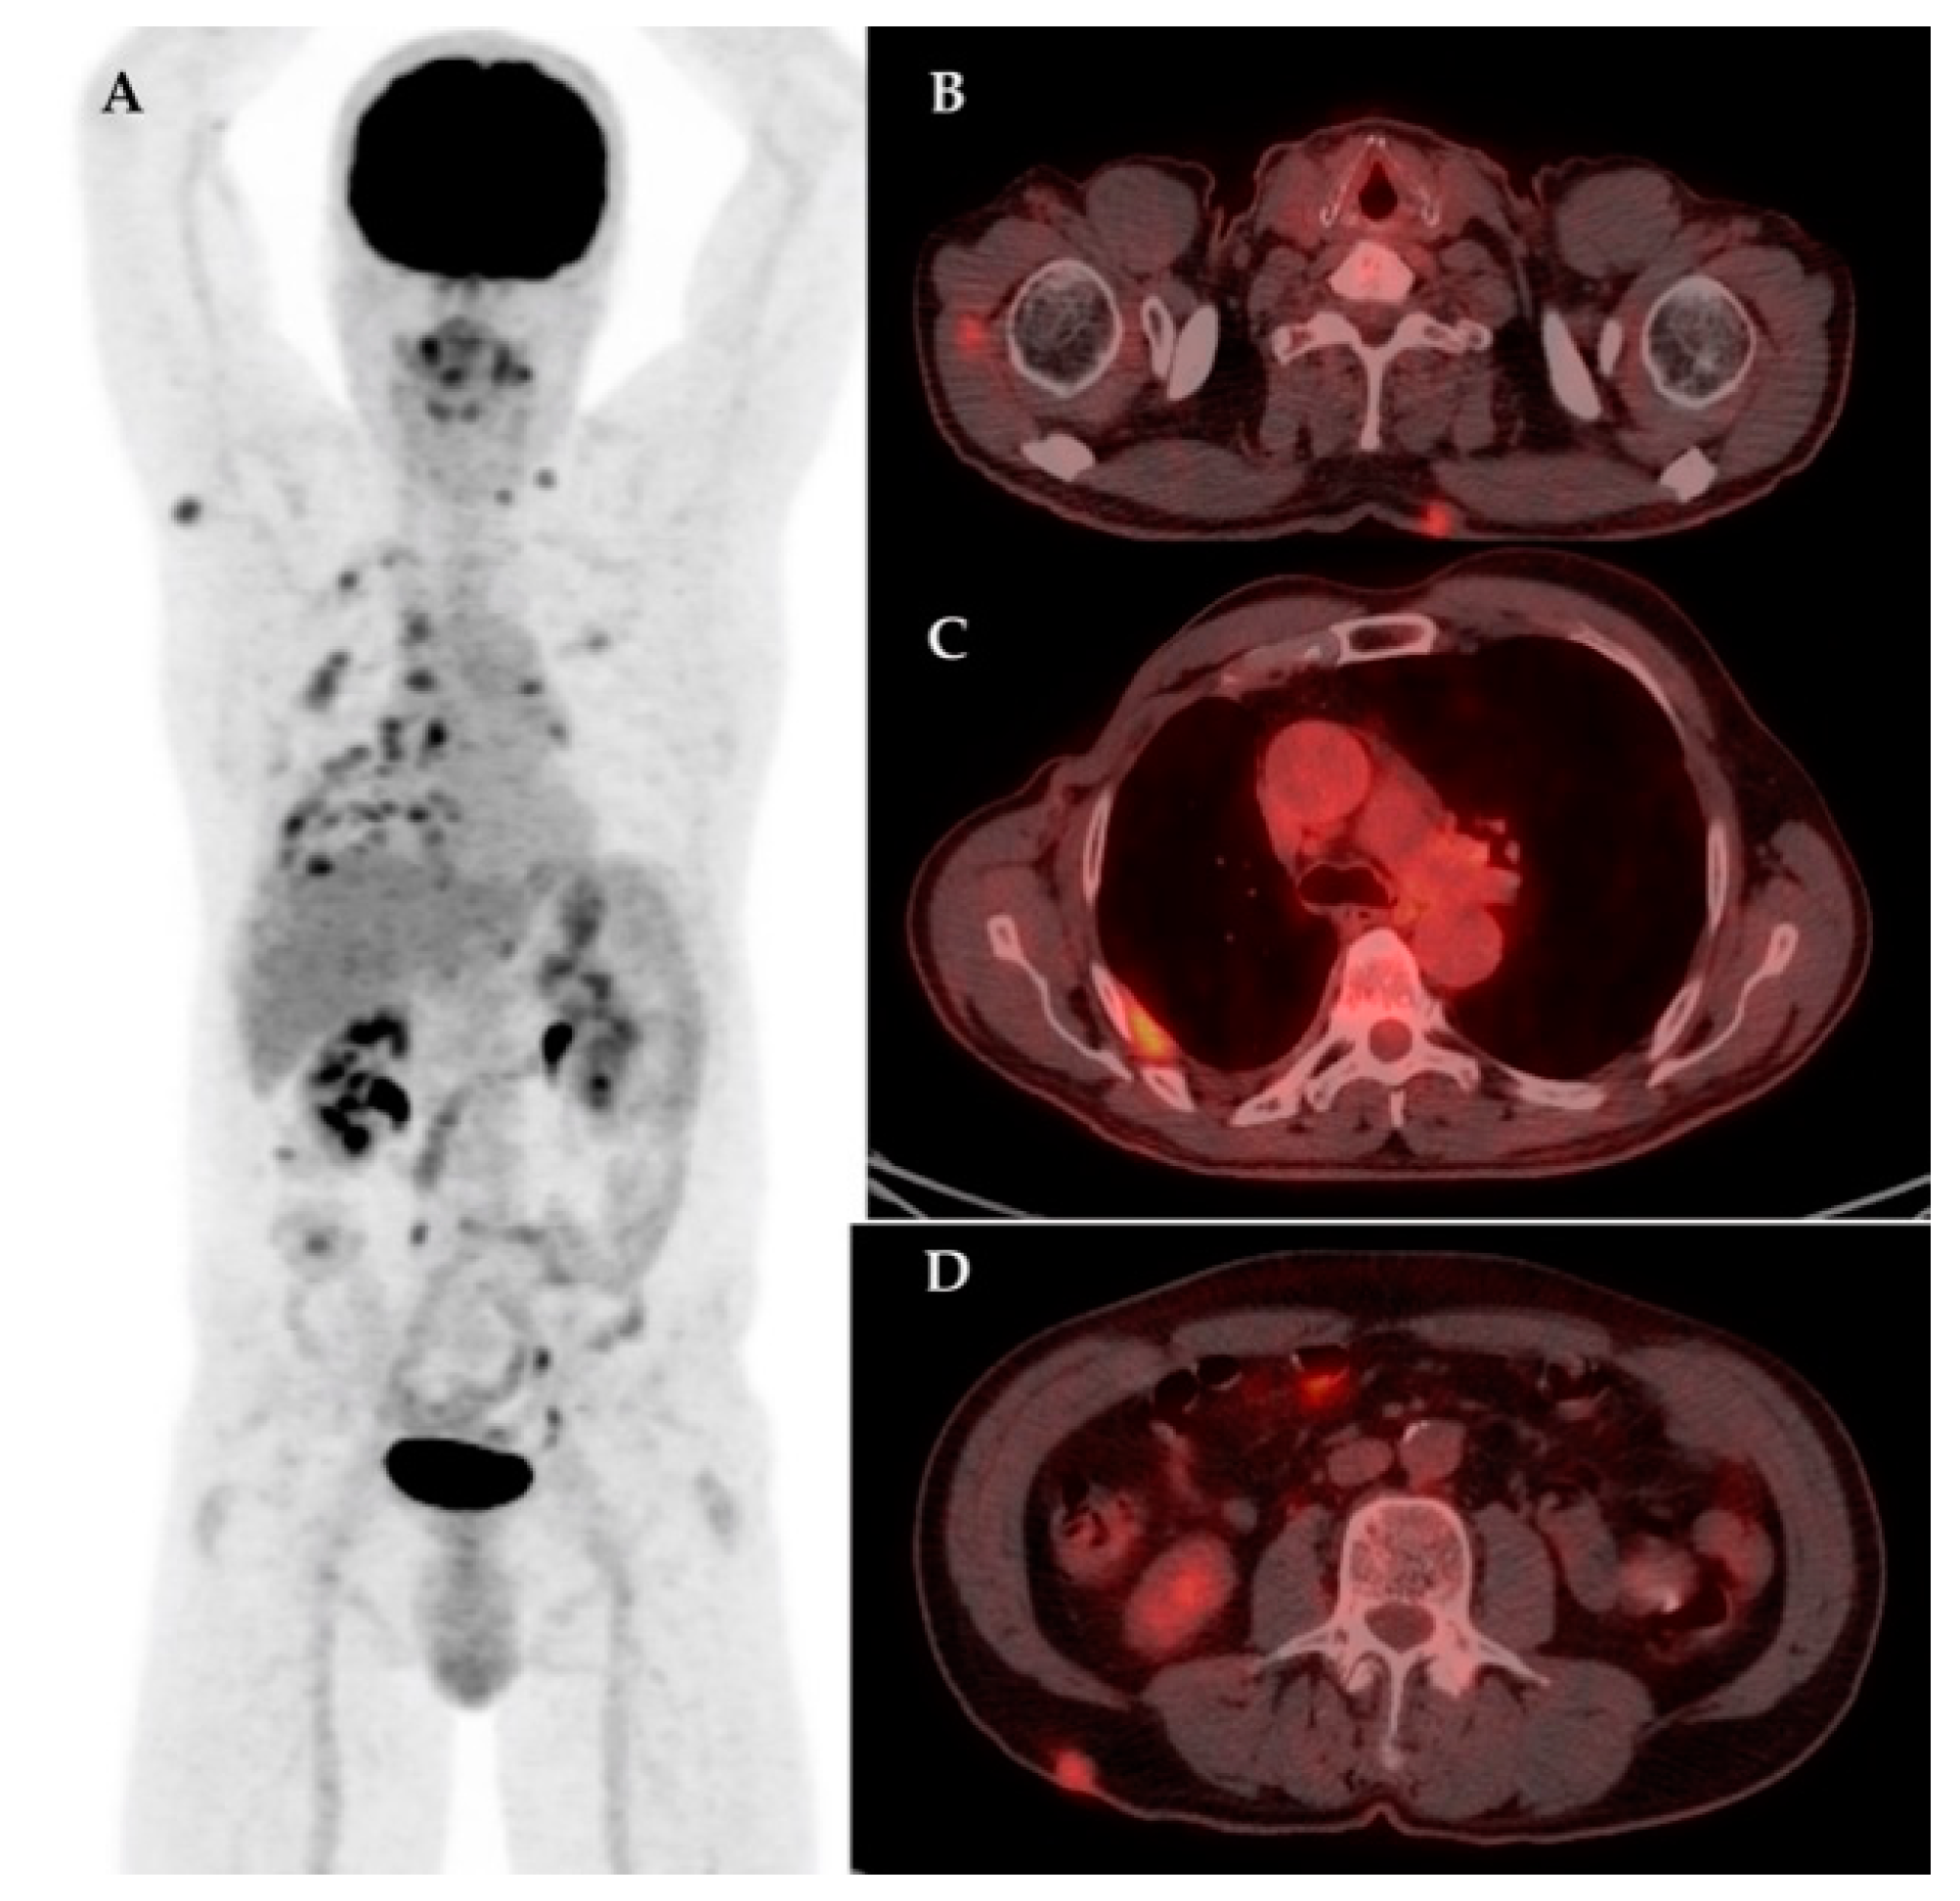

| 7 | 47 | IDC | Biopsy | – | Yes | IIIC | LN | Bn, Sk | 18.36 | – | – |

| 17 | 61 | IDC | RM + ALND | Yes | Yes | IIIB | LN | LN, Lu, M, Bn | 3.1 | Hodgkin Lymphoma | 11.6 |